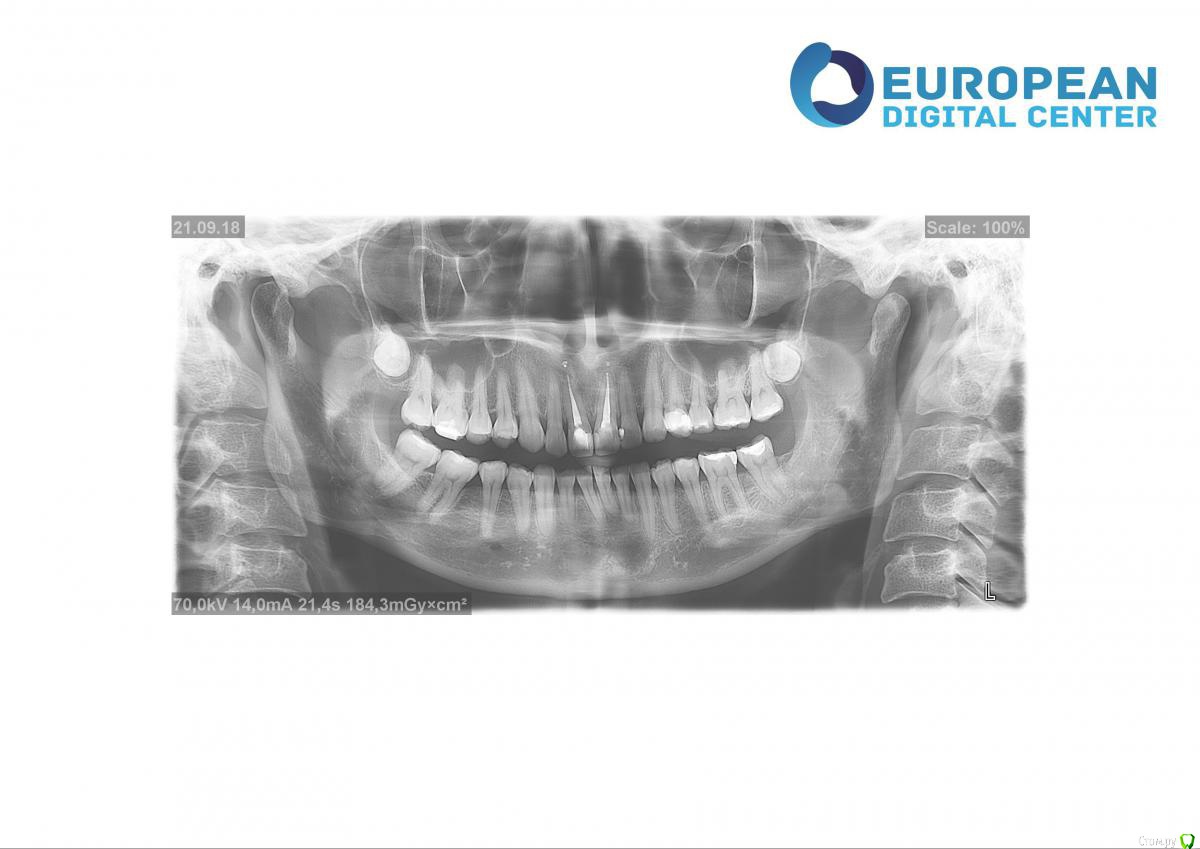

Kema Опубликовано 25 сентября, 2018 Автор Поделиться Опубликовано 25 сентября, 2018 У меня нет нижней правой шестёрки. Правая восьмёрка подвинула семёрку, семёрка наклонилась. Левая ретинированная восьмёрка удалена. На правой стороне жевать неудобно. Ещё верхние зубы наклонились вперёд. Начитавшись про ортогнатические операции хотела узнать показана ли мне она. Ссылка на комментарий